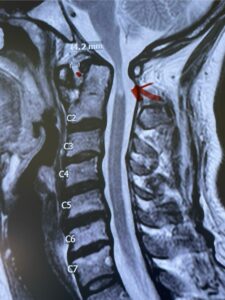

This is a 42 year-old female who presents with severe progressive weakness and numbness and difficulty with balance over a 6-month period. She has a history of having a motor vehicle accident at 5 years old but was never imaged. On exam she was noted to be severely myelopathic. Imaging revealed severe spinal cord compression at the level of C1 (Figs 4a and b).

Fig. 4a: Sagittal T2-weighted cervical MRI demonstrating severe cord compression with myelomalacia of upper cervical spinal cord (red arrow). Notice the increased atlanto-dens interval (red dot).

Cervical x-rays revealed a significantly increased atlanto-axial interval (Fig. 5) On review of her imaging studies it was noted that the right C2 isthmus was very thinned by the vertebral foramen (Figs 6a, b, and c) which would make an attempt at placing a C2 pars screw dangerous. A decision was made to perform an occipital-cervical fusion because only possible unilateral fixation and an extensive C1 laminectomy to be performed eliminating a fixation point if a more traditional C1-C2 was performed. Even if C1 lateral mass screws were able to be placed one could only perform a unilateral screw construct fixation to C2. We performed an occipital cervical fusion down to C4 to get enough inferior fixation and C1 laminectomy. The decompression went well. We placed a left unilateral pars screw and bilateral C3 and C4 lateral mass screws. We placed three 12 mm screws in the midline keel (Fig. 7). Postoperatively the patient had all around improvement in her symptoms and did not qualify for rehab. Her post op films at 6 weeks (Fig. 8)